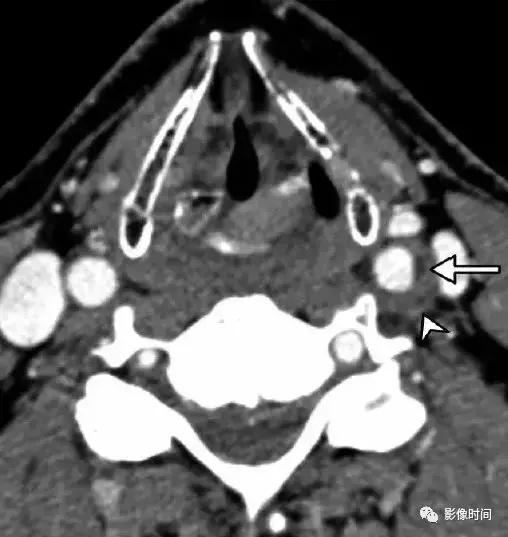

7.短暂颈动脉周围炎症:也称为 Fay 综合征,患者多表现为单侧颈总动脉分叉区域持续性搏动疼痛,具有自限性,往往 1-2 周缓解,首选激素治疗。虽然目前发病机制存在争议,但是大多数认为与颈总动脉分叉区域的特发性炎症有关,因此,又被称为短暂颈动脉周围炎症。CT、MRI 显示颈动脉周围软组织异常、劲动脉壁增厚,特别是分叉处,管腔一般不受影响,CT 一般为低密度,T1WI 压脂序列呈稍低信号(区别于夹层高信号),增强扫描呈明显强化,激素治疗随访后消失。

CTA 显示轴向左侧颈总动脉分叉区周围软组织增厚(无尾箭头),管腔未见狭窄,可见软斑块(长箭头)。TOFMRA 显示左颈内动脉周围软组织增厚,注意右颈内动脉的正常外观。冠状 T1WI+C 显示左侧颈内动脉周围明显强化 (长箭头),注意右颈内动脉的正常外观。激素治疗随访约 4 个月后,冠状 T1WI+C 显示颈内动脉周围厚度减轻。